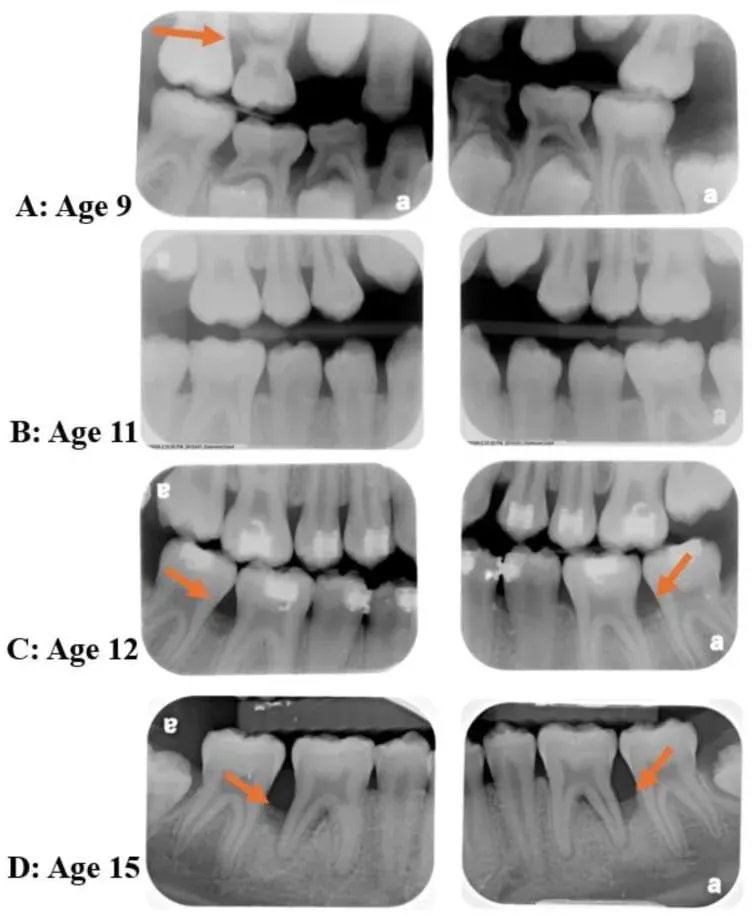

Vediamo ora delle radiografie caratteristice di questa condizione (immagine copyright Miguel and Shaddox, 2024 - licenza CC4.0).

Da queste radiografie di una persona molto giovane, seguita dai 9 ai 15 anni, si evince la grave distruzione estesa dell’osso alveolare, in particolare sui siti molari (frecce rosse).